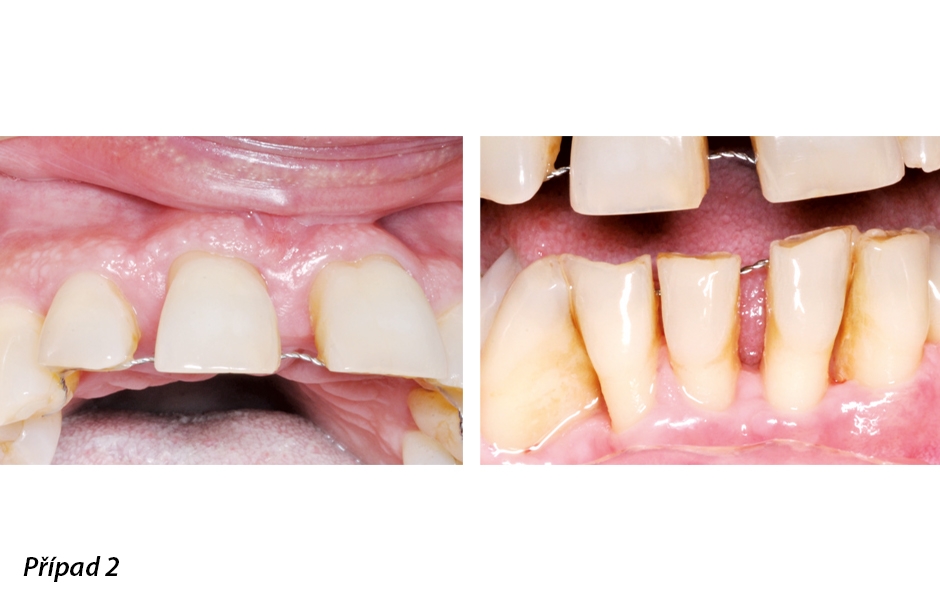

62letá žena si stěžovala na masivní krvácení dásní v celých ústech po dotyku. RTG snímky odhalily parodontitidu a kombinaci vertikálního a horizontálního úbytku kosti. Z důvodu úbytku kosti a středně těžkého zánětu trpěly zuby mobilitou prvního stupně, což byl důvod, proč jsme horní a dolní frontální zuby před chirurgickým zákrokem zdlahovali. Kromě fixace jsme provedli podpůrnou nechirurgickou léčbu. Při chirurgickém zákroku jsme dekontaminovali povrchy kořene profylaktickým pískovačem.

Průměrné parametry před chirurgickým zákrokem (obr. 7–12): PPD (mm): 3,2 | GR (mm): 0,5 | BoP (%): 50 | PI (%): 40 | CAL: 2,7

Počáteční stav